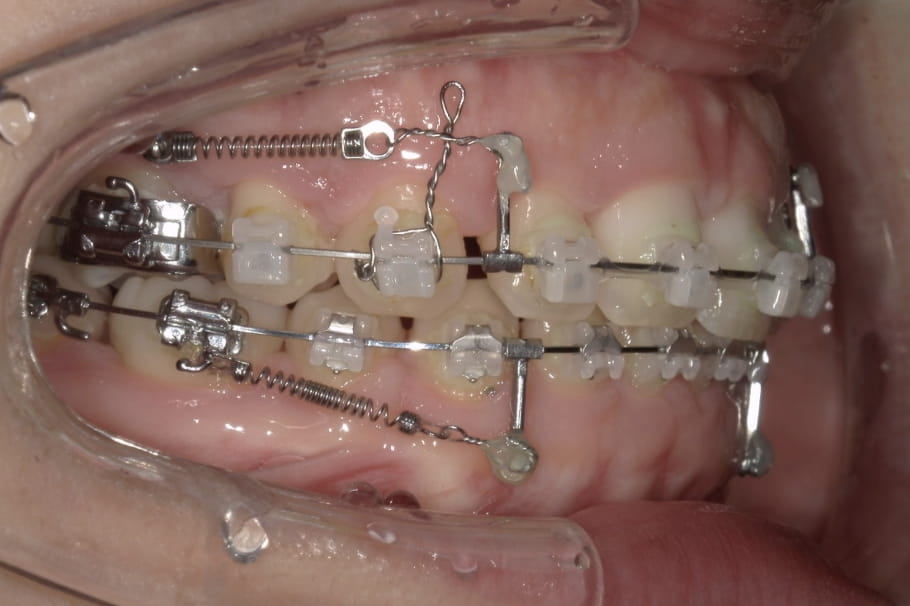

《歯槽性上下顎前突を伴う叢生》

症例42

性別:女性 年齢:13歳 お住まいの地域:奈良市

主訴 上の2本が出てるのが気になる

治療装置 上裏側、下表側からのハーフリンガル矯正装置

抜歯 上下4本

治療期間 2年8ヶ月

診断名 歯槽性上下顎前突を伴う叢生

副作用 歯肉退縮・歯根吸収・歯髄壊死・癒着による予期せぬ歯の動き

より綺麗にする希望を達成するために上下4本を抜歯。前歯のリトラクション(後方移動)を行うためにインプラントを使用。若年層ではあるが、インプラントの安定がよく、ヘッドギアに切り替えることなく、順調に進められた。

治療中(19ヶ月後)